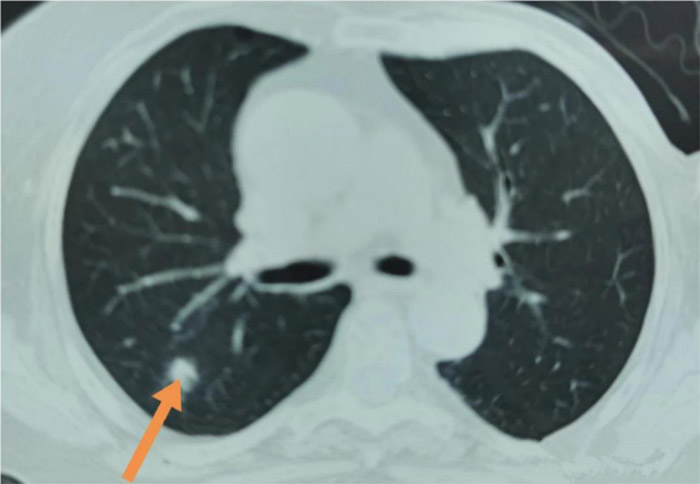

这位阿姨75岁,体检发现右肺上叶结节,直径约1.2cm,边缘欠规则,无毛刺及分叶,无胸膜牵引。体检中心的医生说,最好到正规医院看一下。

阿姨带着胸部CT片子和满心的焦虑来到了丹东市第一医院胸外科门诊,我院的医生在仔细查看胸部CT后,认为单从CT影像上看,这属于一个不确定性结节,建议阿姨化验“肺小结节自身抗体检测”,看看有没有激发肿瘤免疫反应。

过了3个月阿姨来复查,胸部CT没有看见任何病灶,她的肺结节完全不见了。阿姨高高兴兴的离开了胸外科诊室。